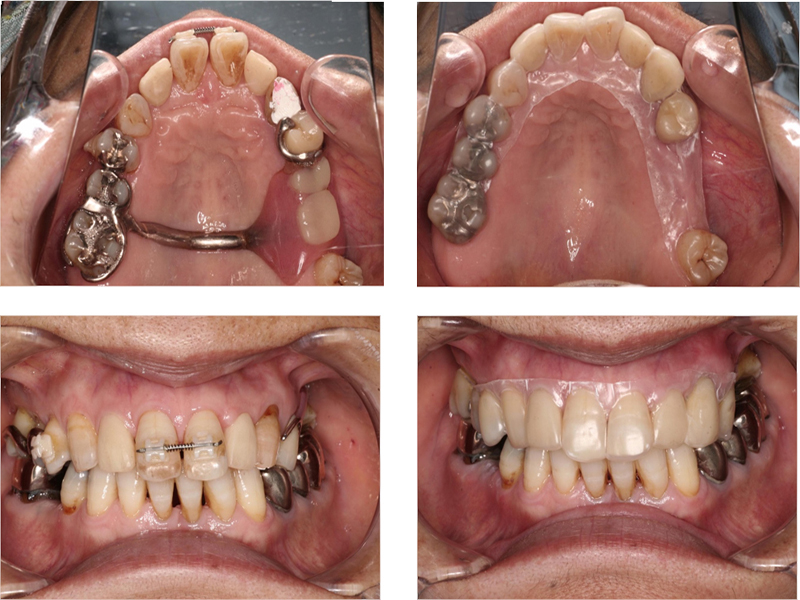

▼ ケース4.Upright症例

初診

治療中

before

after